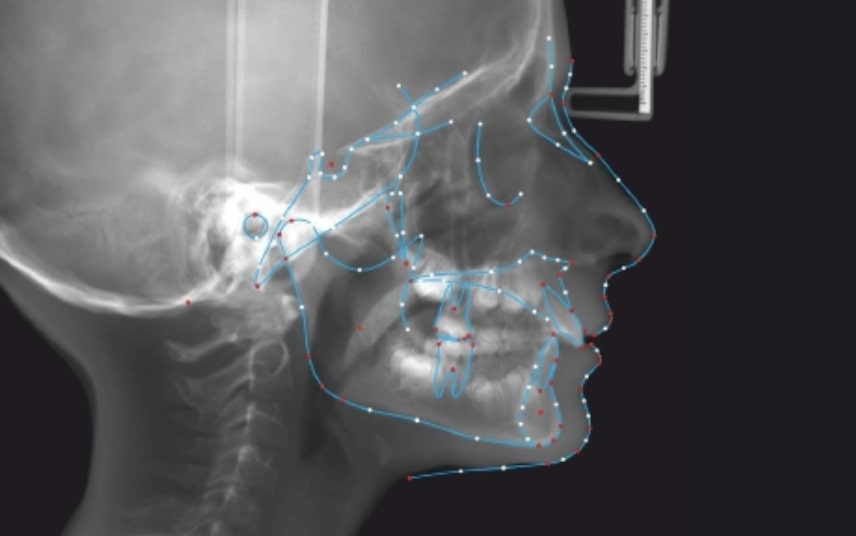

Clinical examination and diagnosis

FACIAL: class 2 profile with Lower jaw deficit

SKELETAL PATERN: Class 2

DENTAL:

- Molar and Canine class 2 on the right side – Molar and Canine clss 1 on the left side

- Increased Overjet

- DeepBite